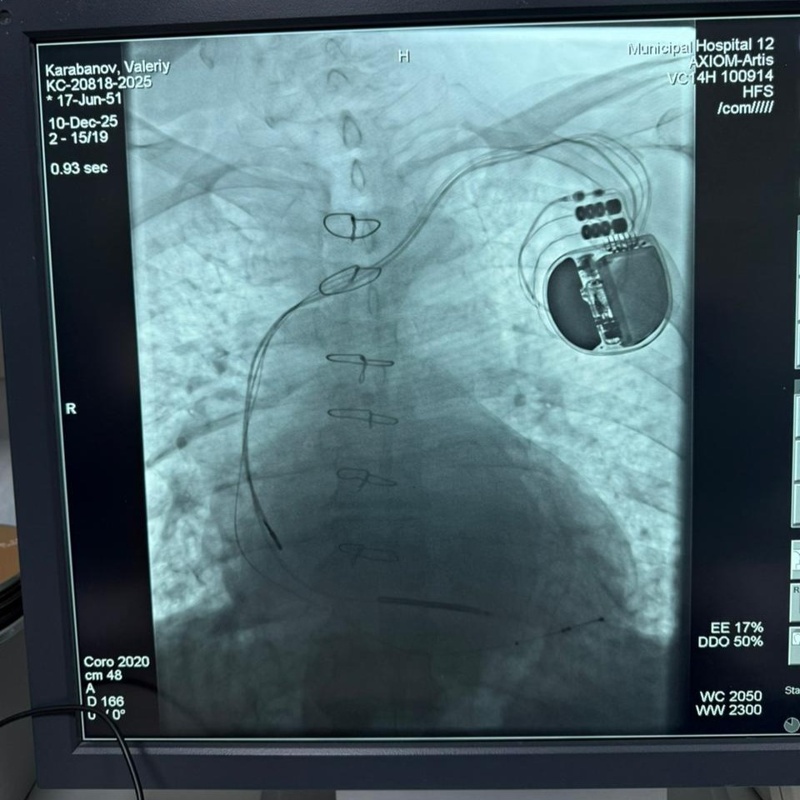

– ИКД имплантациясы жергілікті анестезиямен жүргізілді. Құрылғы бұғана асты аймағына орнатылып, электродтар қан тамырлары арқылы жүрек қуыстарына жеткізілді. Қауіпті ырғақ бұзылысы туындаған жағдайда құрылғы оны автоматты түрде анықтап, дереу әсер етеді және жүректің қалыпты жұмысын қалпына келтіреді. Кардиовертер-дефибриллятор науқасты өмірін стационарда да, ауруханадан шыққаннан кейін де тұрақты түрде қорғауды қамтамасыз етеді, - деп түсіндірді аурухана аритмологы Ғани Төлепбергенов.